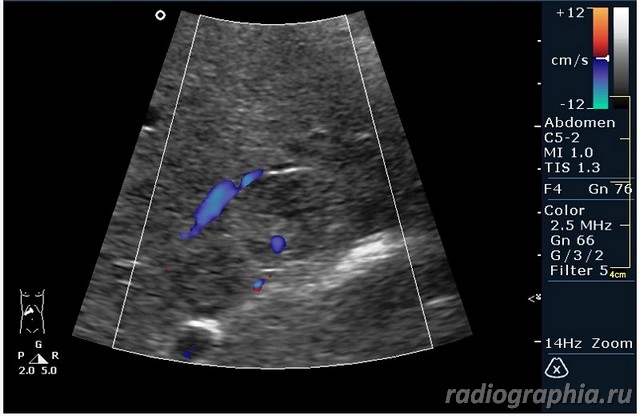

гемангиома,рядом питающий сосуд

Мне тоже нравится версия, что это - гемангиома.Нелли писал(а):гемангиома,рядом питающий сосуд